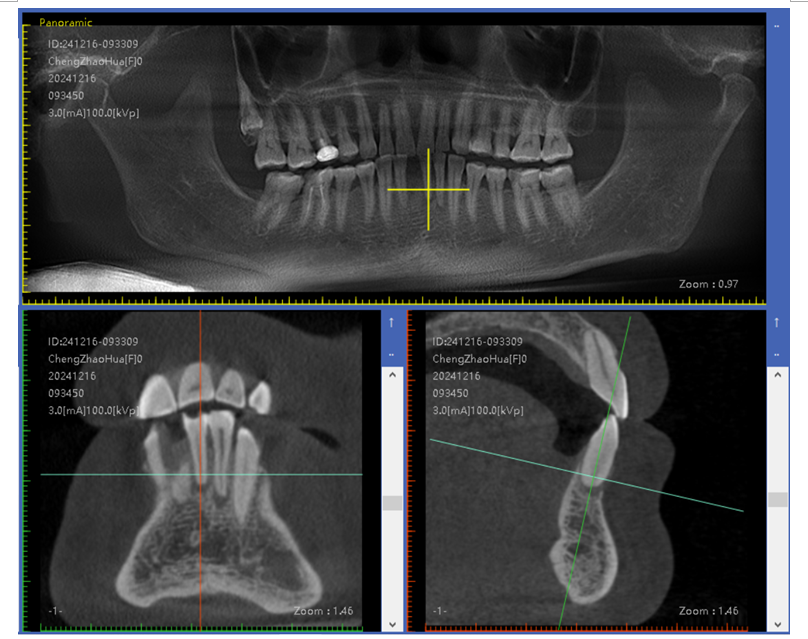

数字化导板技术:通过口腔 CT 扫描获取患者口腔颌骨的精确三维数据,利用计算机辅助设计(CAD)和计算机辅助制造(CAM)技术制作出个性化的手术导板。在牙槽外科手术中,如拔牙、种植牙等,导板可以精确引导手术器械的操作,提高手术的准确性和可预测性,减少手术创伤和并发症,同时缩短手术时间。

即刻种植与即刻修复技术:在拔牙后立即将种植体植入拔牙窝内,并在种植体植入后短期内(通常在数天至数周内)完成牙冠修复。这种技术可以减少患者缺牙的时间,避免牙槽骨因缺牙而发生吸收,同时能够更快地恢复患者的咀嚼功能和美观。

自提牙移植技术:是将患者自身的牙齿从一个位置移植到另一个需拔除患牙或缺失牙的位置上,使其在新位置愈合后行使咬合功能,恢复牙列缺损